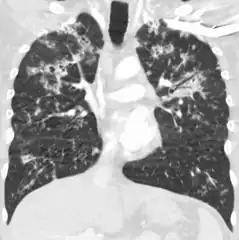

Miliary tuberculosis is a form of tuberculosis that is characterized by a wide dissemination into the human body and by the tiny size of the lesions (1–5 mm). Its name comes from a distinctive pattern seen on a chest radiograph of many tiny spots distributed throughout the lung fields with the appearance similar to millet seeds—thus the term "miliary" tuberculosis. Miliary TB may infect any number of organs, including the lungs, liver, and spleen.[2] Miliary tuberculosis is present in about 2% of all reported cases of tuberculosis and accounts for up to 20% of all extra-pulmonary tuberculosis cases.[3]

Testing for miliary tuberculosis is conducted in a similar manner as for other forms of tuberculosis, although a number of tests must be conducted on a patient to confirm diagnosis.[4] Tests include chest x-ray, sputum culture, bronchoscopy, open lung biopsy, head CT/MRI, blood cultures, fundoscopy, and electrocardiography.[10] The tuberculosis (TB) blood test, also called an Interferon Gamma Release Assay or IGRA, is a way to diagnose latent TB. A variety of neurological complications have been noted in miliary tuberculosis patients—tuberculous meningitis and cerebral tuberculomas being the most frequent. However, a majority of patients improve following antituberculous treatment. Rarely lymphangitic spread of lung cancer could mimic miliary pattern of tuberculosis on regular chest X-ray. [15]